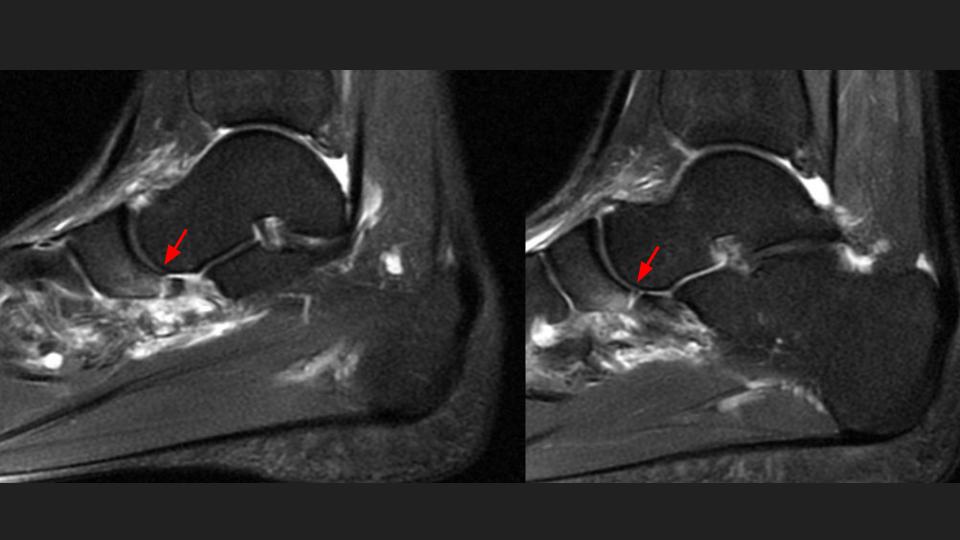

28F runner felt pop and pain after injury 3 days ago

There is an avulsion fracture of the plantar margin of the navicular at the insertion of the inferior plantar longitudinal component of the Spring ligament complex. Never seen this before. Reference article.

spring ligament ( RID3052 )